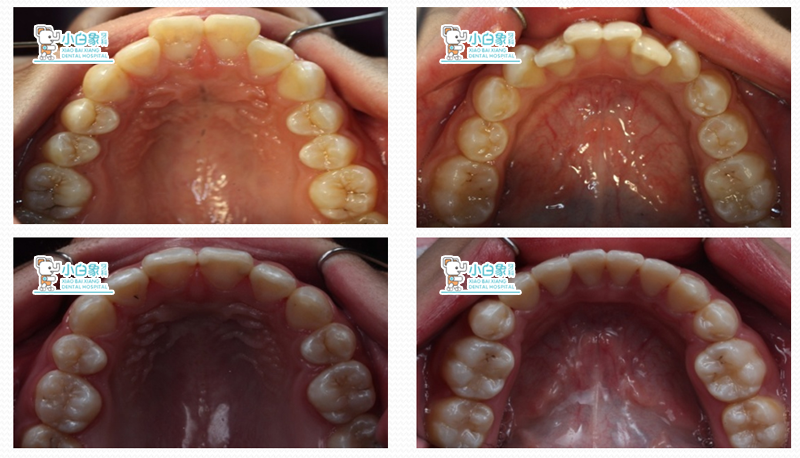

治疗后

治疗后测量

总结:

总体来说比较满意。

上颌突度改善较大,面型有改观,咬合关系从二类变为一类,深覆合、深覆盖得到很好的解决。

不足:下前牙角度没有控制好,倾斜度较大。